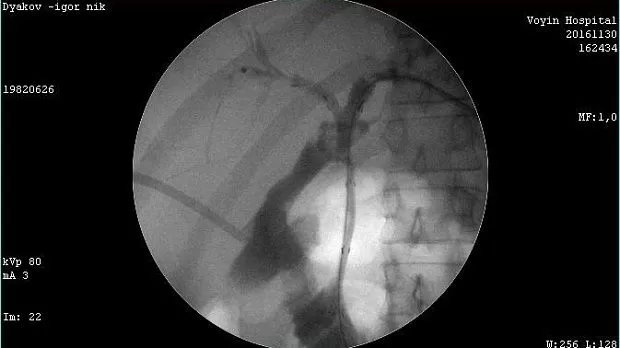

Молодой человек 33 г. Диагноз подтвержден. Стентирован пластиковыми стентами, потом самораскрывающимися. Одномоментно анте и ретроградно - с хорошим результатом. Дальше был поставлен в очередь на трансплантацию. Дальнейшая судьба не известна.